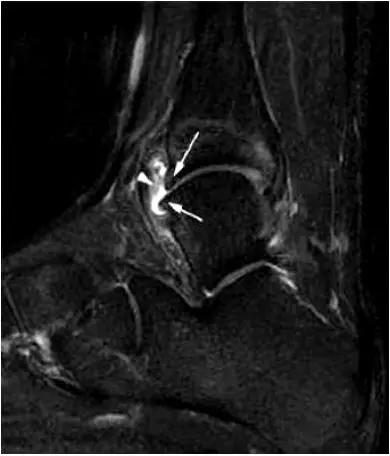

6.后踝撞击综合症:

- 骨性撞击多见,例如距骨后三角骨损伤,距骨或跟骨后突过度增生。软组织撞击表现为后胫腓韧带下部分、横韧带、后踝间韧带的撕裂或肥厚增生。

- 影像学表现为距骨后三角骨的存在或损伤以及距骨后突骨赘形成,导致踝关节跖屈受限,可伴随拇长屈肌肌腱鞘炎症及邻近滑膜不同程度的炎性增生 。

- MRI 检查示距后三角骨及周围软组织有水肿信号,距后三角骨和距骨之间正常的低信号纤维连接中断,出现液性信号。

3、MR表现:

- 三角籽骨或距骨后三角结构模糊和变形,T1WI信号降低, T2WI信号升高,

- 周围脂肪水肿,

- 踇趾长屈肌腱信号升高,见鞘膜积液,

- 胫骨后下跟骨上缘骨结构形态变化和信号异常,

- 三角籽骨和距骨退行性囊变。

三角籽骨综合征

三角籽骨综合征并跟腱滑囊积液